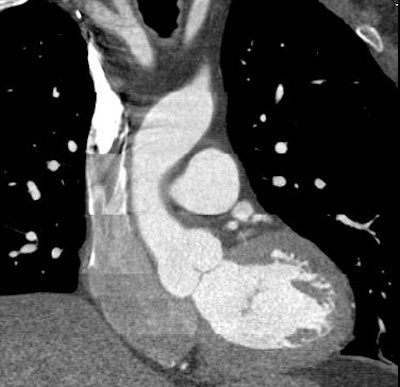

![]() |

| Top, triple or multirule-out CTA in a patient with atypical pain but normal arteries shows good opacification in all three arterial beds (coronary, pulmonary, aorta). Below, CTA of a low-risk patient with chest pain shows typical "vulnerable plaque" with little stenosis and positive remodeling. Bottom, triple rule-out scan in a patient presenting with atypical chest pain reveals aortic dissection. |